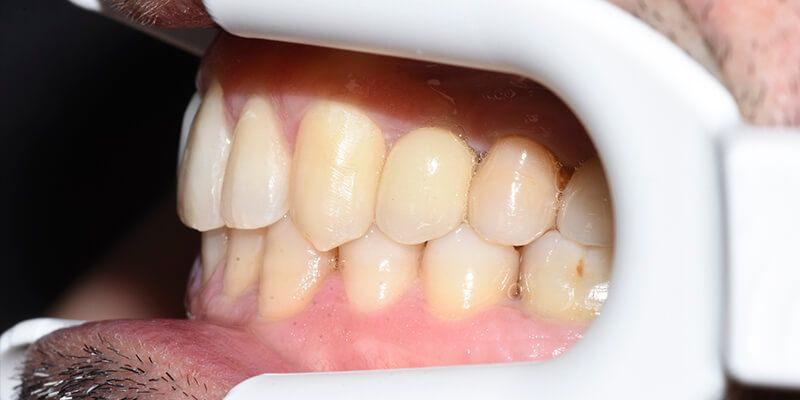

Paciente de 46 años acude a la consulta interesado en reponer las piezas ausentes.

En la primera visita se le diagnostica y presupuesta la exodoncia de restos radiculares en 17 y 26 y la realización de curetajes en ambas arcadas, así como la obturación de 2 caries proximales en 27 y 37.

También se le explica la necesidad de una fase ortodóncica previa a la reposición protésica de las piezas ausentes 14,24,26 y 46, cuyo objetivo es la alineación del sector anterior superior y la intrusión del mismo, especialmente del 23 y el cierre de los diastemas presentes, centrando la línea media y mejorando los espacios para la colocación de los respectivos implantes y sus correspondientes coronas.